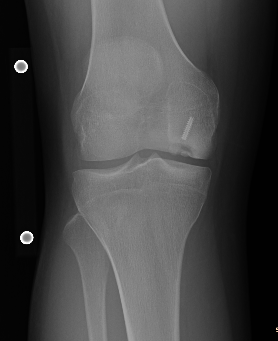

Young varus with OA Failed medial OCD with varus